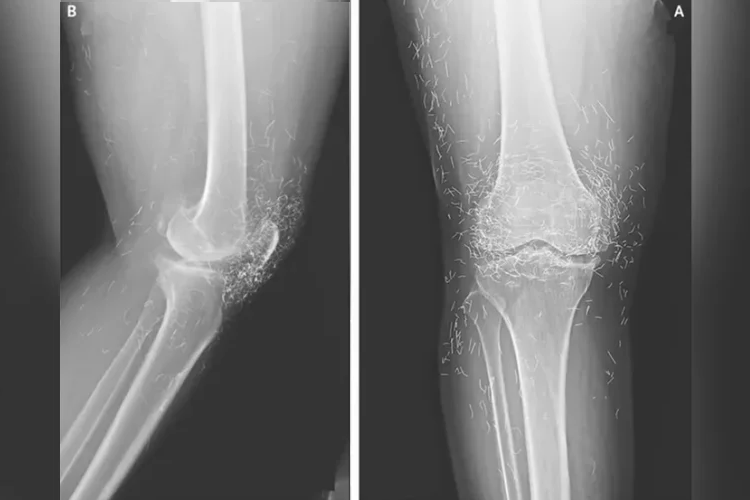

Фото: The New England Journal of Medicine

Рентгеновское исследование выявило утолщение и уплотнение внутренней части большеберцовой кости, костные разрастания в колене – все типичные симптомы остеоартрита, – а также сотни крошечных золотых нитей, вросших в ткани вокруг колена. Врачи предупреждают, что акупунктура золотыми нитями не имеет научно доказанной пользы для пациента, но сопряжена со множеством известных рисков. Крошечные нити могут вызывать образование кист, мигрировать в организм и повреждать окружающие ткани, а также сделать невозможным проведение МРТ, потенциально спасающей жизнь, из-за риска смещения металла и повреждения кровеносных сосудов.